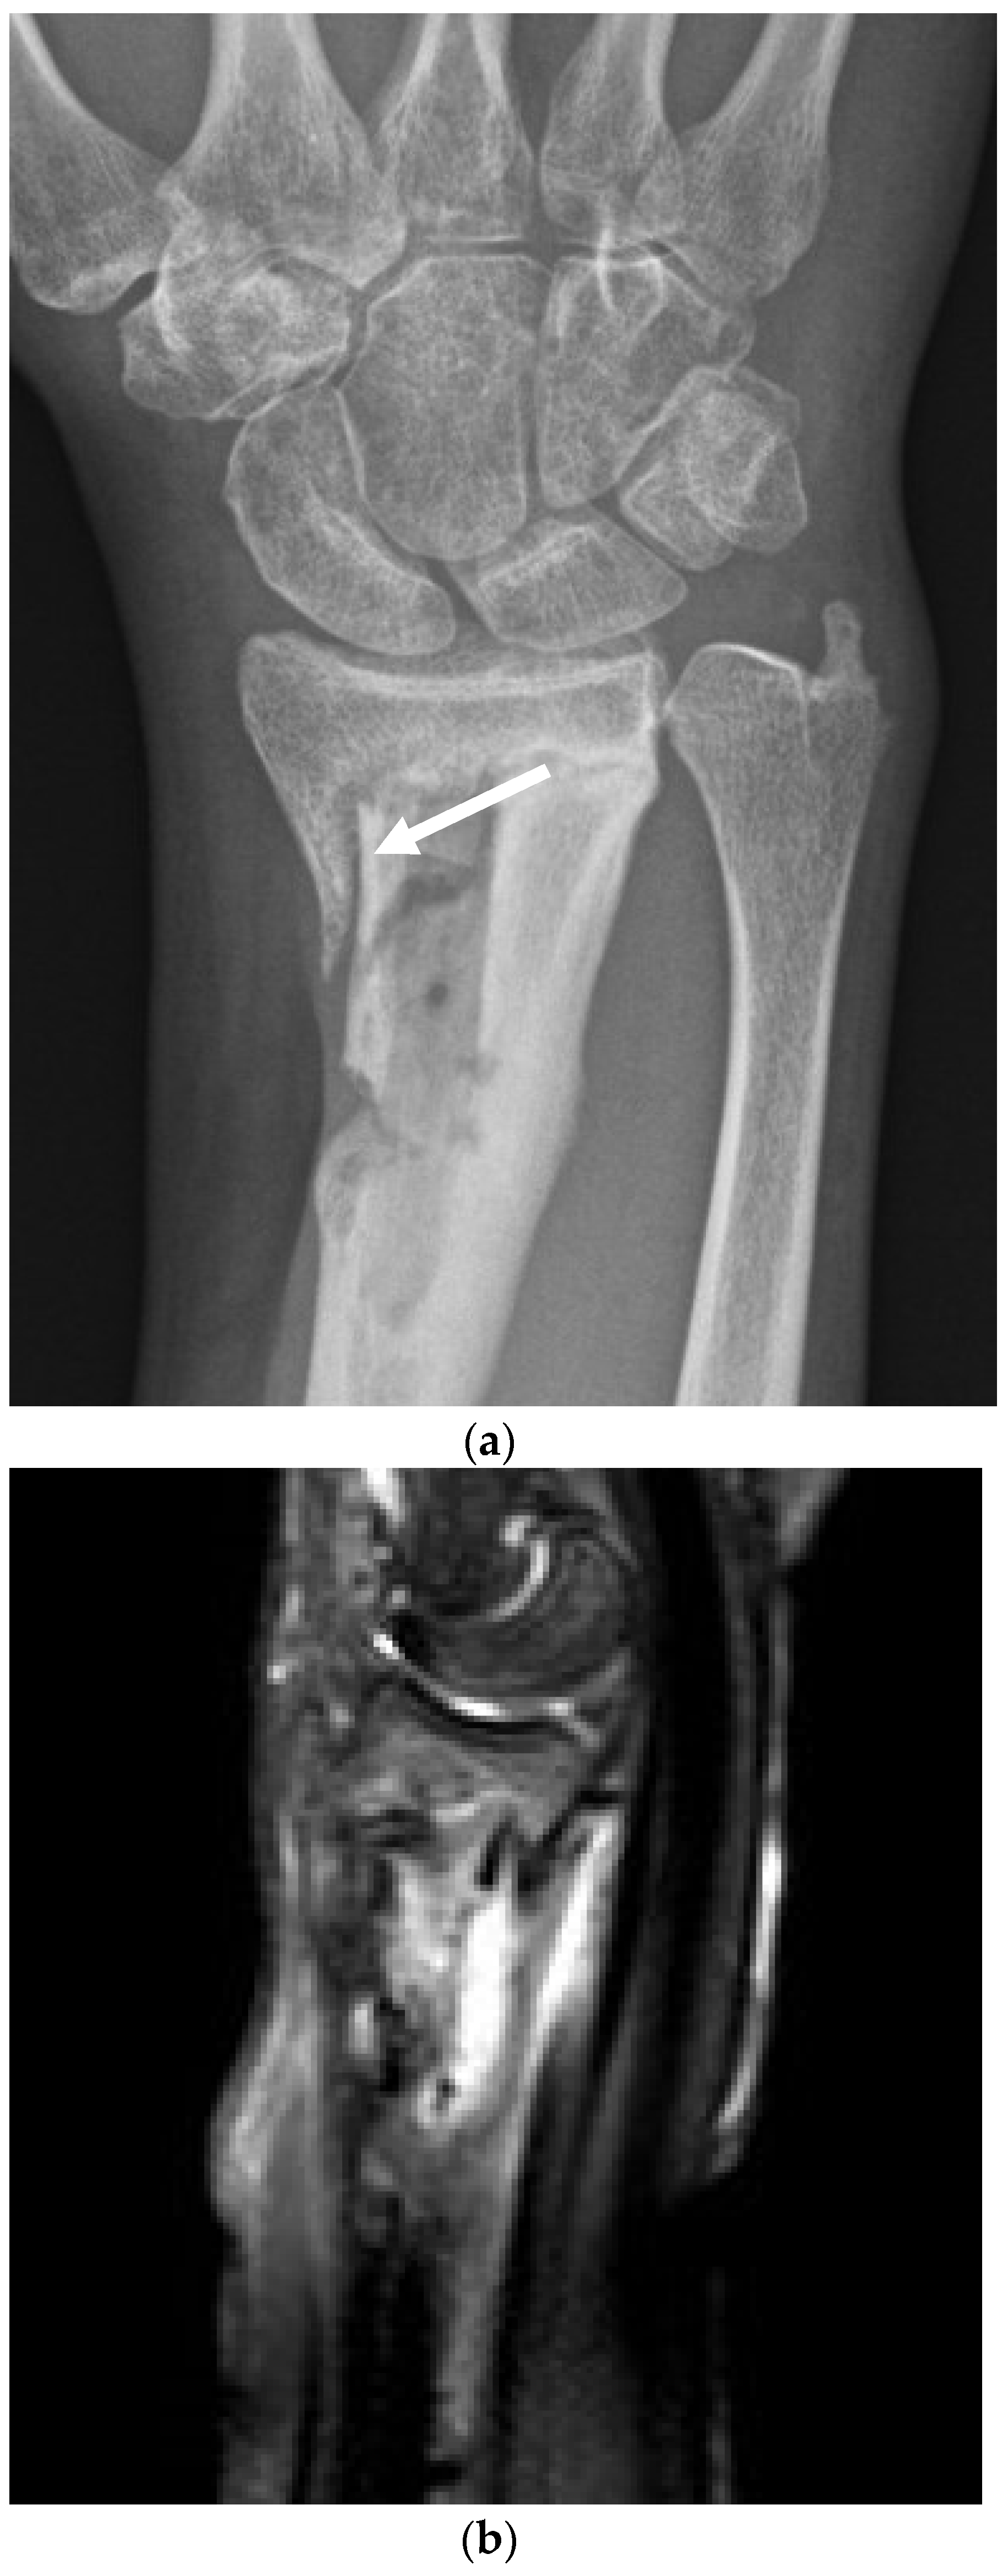

All patients were treated with a single-stage protocol incorporating deep tissue sampling, excision of dead and compromised tissue, management of the excised dead space, bone stabilization (if required) and soft tissue closure, as previously described [32] (Figure 2a–e).

Figure 2.

(a). The surgical management with implantation of a gentamicin-loaded antibiotic carrier. This 32-year-old woman suffered a closed fracture of her distal radius in a fall. After fixation with a plate, the fracture became infected. The plate was removed, but she continued with a draining sinus and active infection. This preoperative radiograph shows the dead bone in the radial metaphysis (white arrow), but the fracture has healed. (b). The magnetic resonance scan demonstrates the area of high signal around the dead bone, with active infection. (c). At operation, the volar aspect of the wrist was opened and the infected bone exposed. Five deep tissue samples were taken for microbiology and three for histology. The central area of necrotic bone and infected tissue (white arrow) was excised back to healthy bleeding bone. (d). The excised dead space has been filled with CERAMENT G (with gentamicin), completely filling the bone defect. The material was compressed into the bone and the skin closed in layers. (e). The postoperative radiograph shows the antibiotic carrier in place, filling the defect.